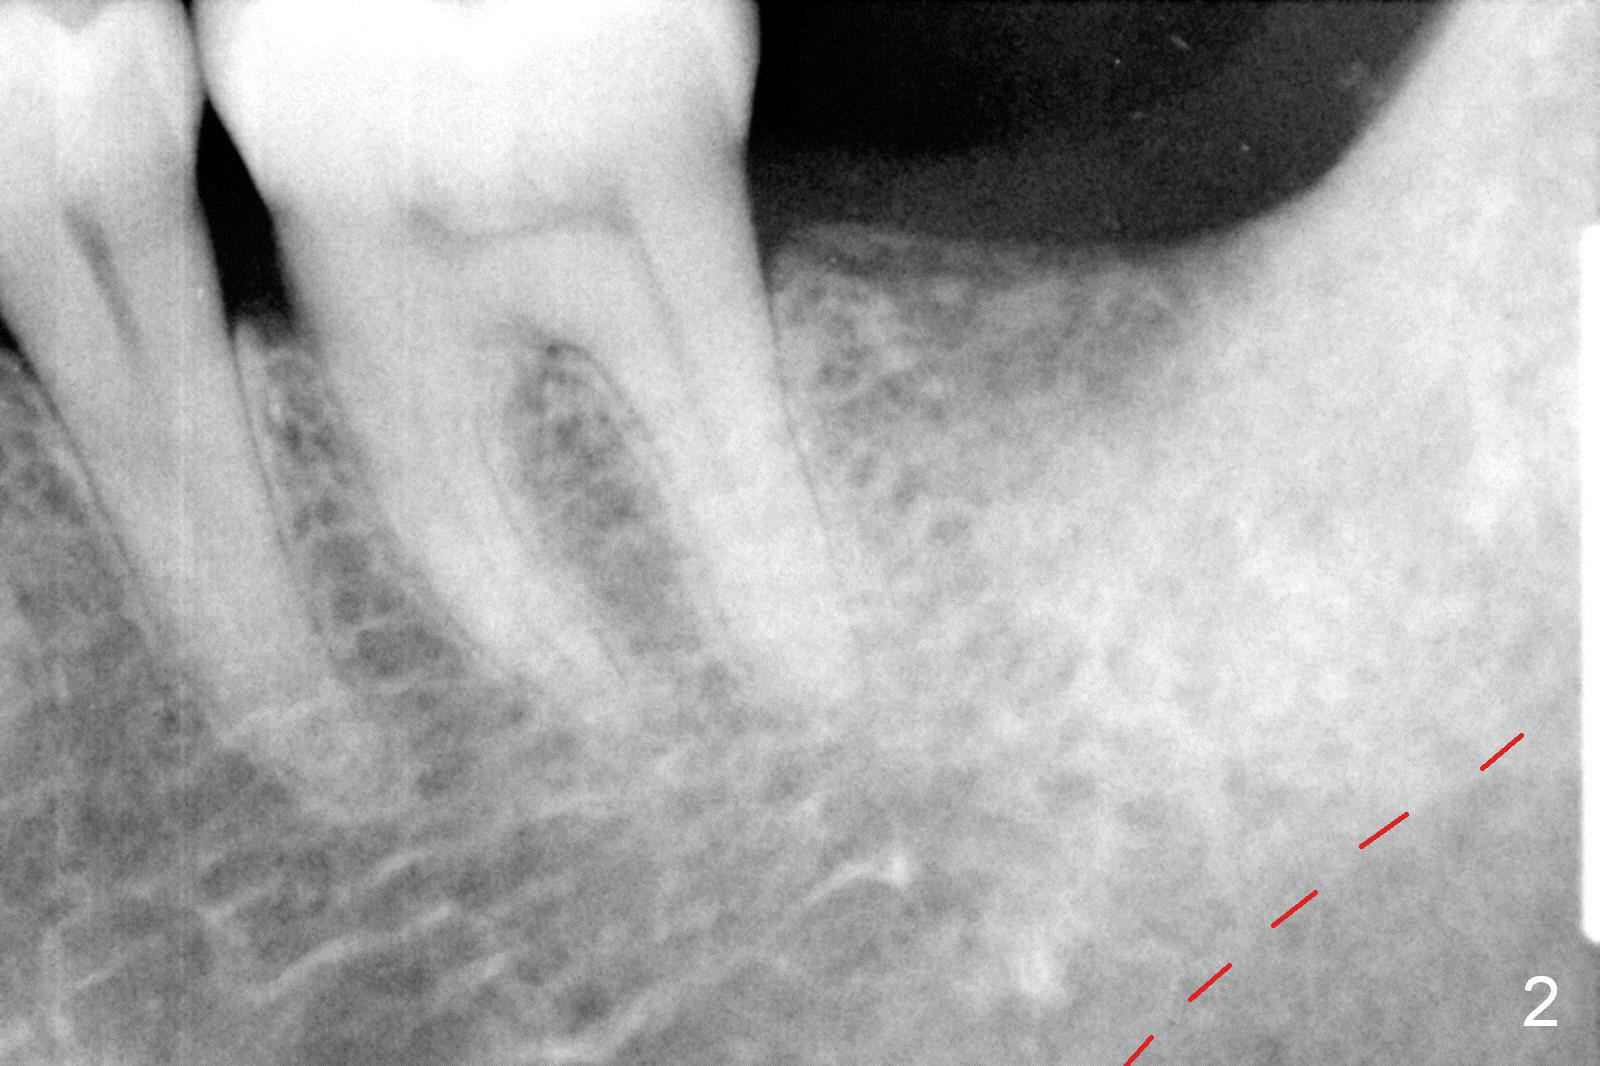

A 48-year-old lady is a dental phobic, requesting extraction of the lower left 2nd molar (Fig.1). She returns for implant placement 9 months post extraction (Fig.2). The ridge is mildly to moderately atrophic. It appears that a 5x12 mm implant is appropriate for the site (Fig.3). For safety, osteotomy is initiated at the depth of 10 mm; it appears that there is enough height for a 12 mm implant (Fig.4). The depth is controlled by drill stopper (Fig.5 S). Finally a 5x12 mm implant is apparently safely placed (Fig.6). A healing abutment is placed and the incision is sutured with 4-0 Chromic gut (Fig.7). Perio dressing is applied around the healing abutment for wound protection (Fig.8). It appears that the healing abutment (Fig.8': *) helps stabilize the perio dressing, which remains in place 1 week postop. When the perio dressing is removed, the wound around the healing abutment is healing (Fig.9). There is no bone loss around the implant 3 months postop (Fig.10 (H: healing abutment), or 16 months postop (i.e., 9 months post cementation, Fig.11,12). The patient complains of pain when she chews with the implant crown, but pain stops whenever she does not bite. Percussion does not elicit any discomfort. The gingiva is healthy. There is possibility of the buccal plate being thin or the lingual plate being perforated in the submandibular fossa. If the discomfort remains the same next 6 months, CBCT will be prescribed.